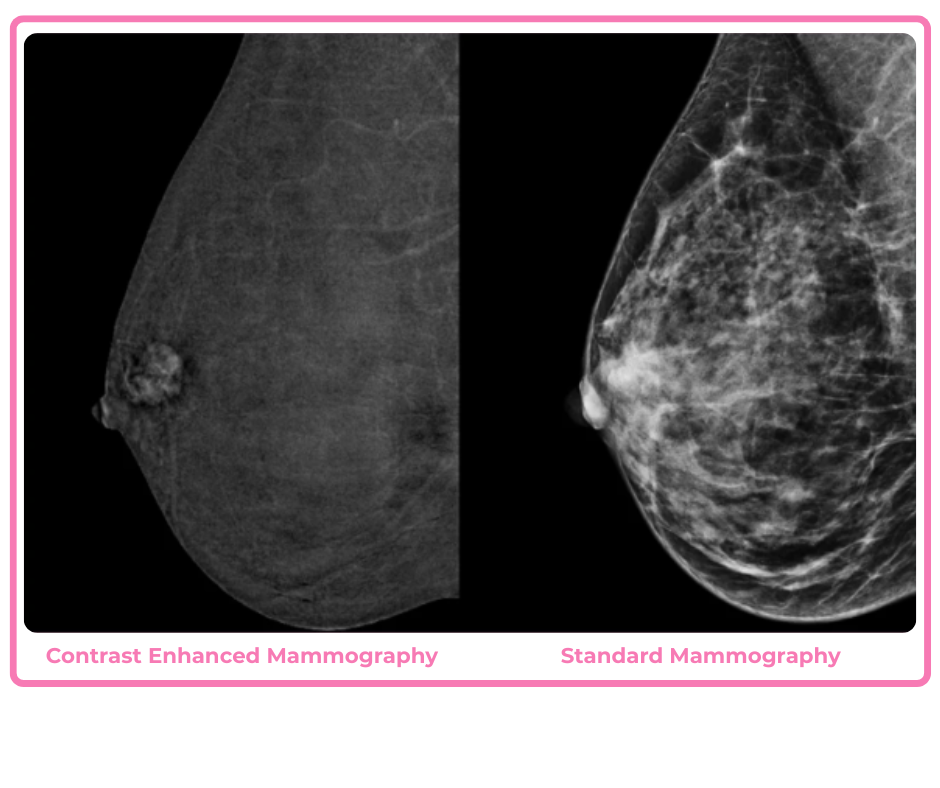

Contrast Enhanced Mammography

Contrast Enhanced Mammography (CEM) is a state-of-the-art breast imaging technique, in which an intravenous contrast agent is injected immediately prior to a ‘dual-energy’ mammogram (two images) being performed. One image is ‘subtracted’ from the other to create an image of the blood distribution in the breast tissues. CEM can improve cancer detection and diagnostic confidence. It is used for a range of problems – for screening patients at increased risk of breast cancer, particularly those with dense breast tissue, for evaluating patients with findings that are difficult to resolve, and for further assessing patients with a diagnosis of breast cancer.

Precautions are taken to identify contrast agent contraindications, as CEM is not suitable for patients who have a known contrast allergy, are pregnant, or have kidney disease. CEM is suitable for patients with breast implants.